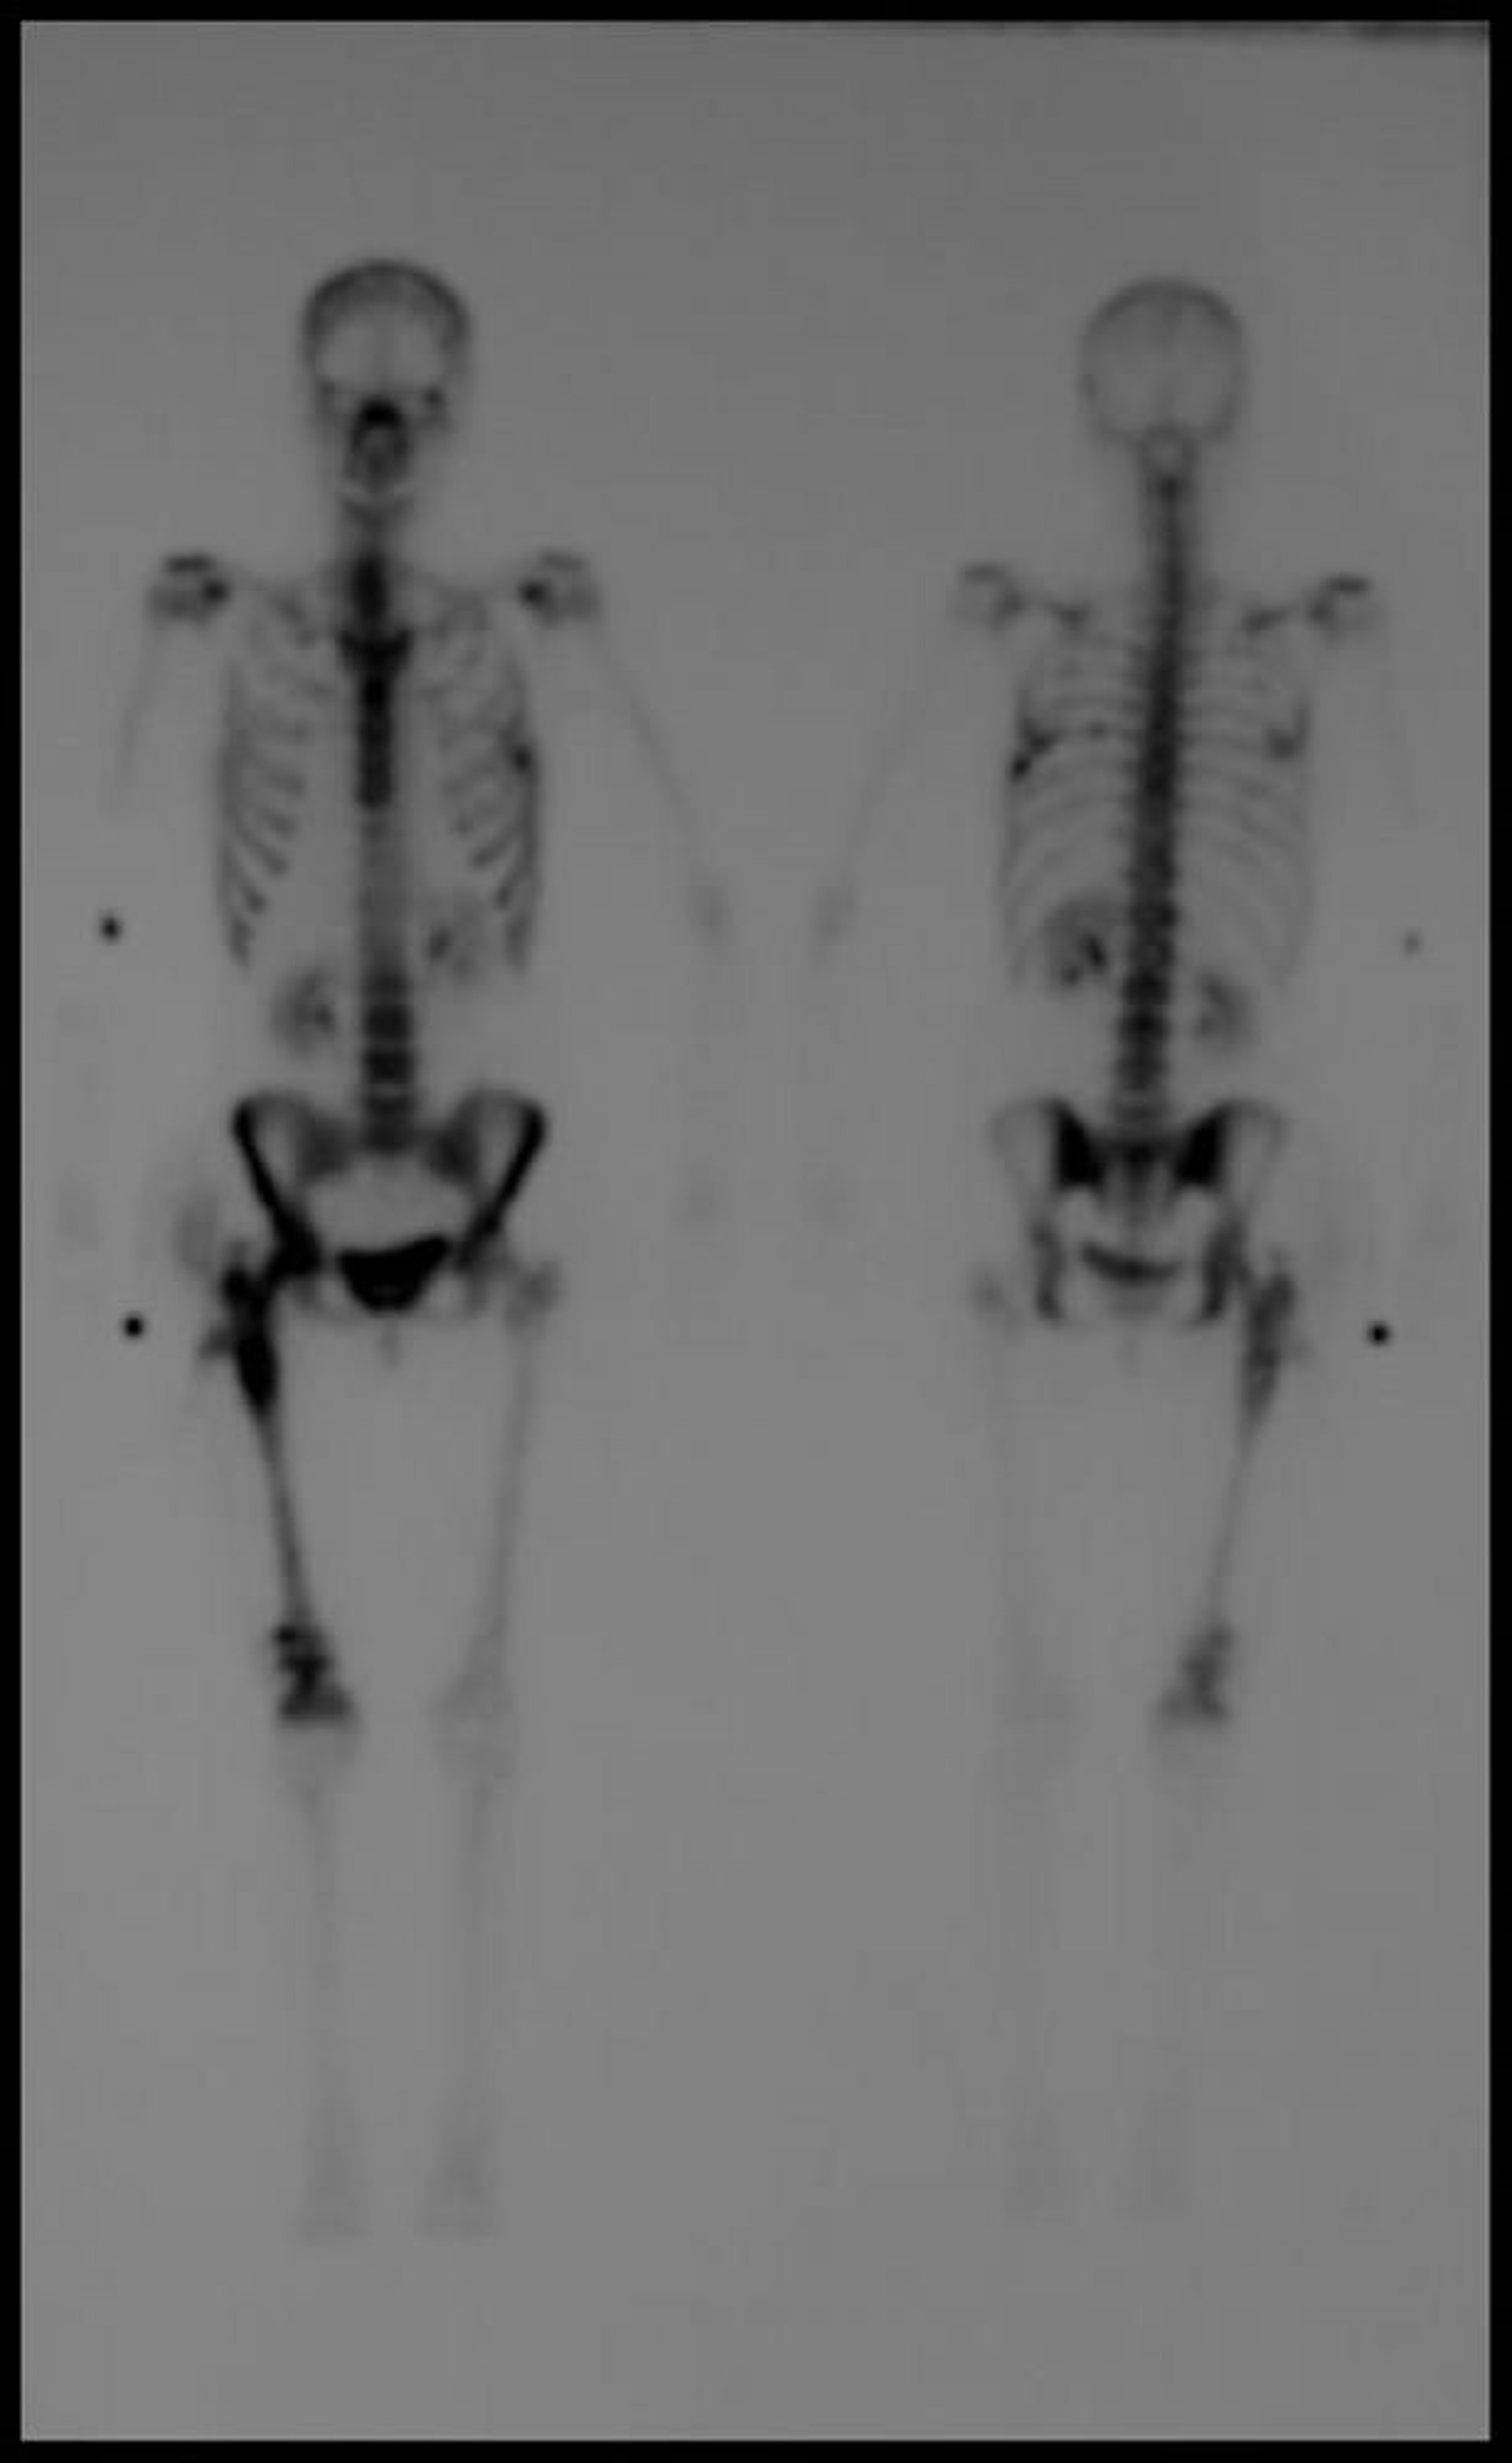

Scintigraphie osseuse de tout le corps

L'image scintigraphique osseuse retardée au technétium-99m montre des foyers multiples d'absorption accrue compatibles avec une maladie métastatique.

Image courtoisie de Hakan Ilaslan, MD.